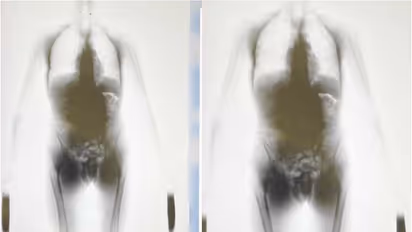

വിശ്വസനീയമായ ഒരു രഹസ്യ വിവരം ലഭിച്ചതിനെ തുടർന്നാണ് അധികൃതർ ഈ ഓപ്പറേഷൻ ആരംഭിച്ചത്. യൂറോപ്യൻ പൗരനായ യാത്രക്കാരൻ വിമാനത്താവളം വഴി മയക്കുമരുന്ന് കടത്താൻ ഉദ്ദേശിക്കുന്നുണ്ടെന്നും. മയക്കുമരുന്ന് ശരീരത്തിനുള്ളിൽ ഒളിപ്പിച്ചതായുമായിരുന്നു വിവരം. കസ്റ്റംസ് ഉദ്യോഗസ്ഥർ ഇയാൾ വിമാനമിറങ്ങിയ ഉടൻ തന്നെ നിരീക്ഷണം നടത്തിയിരുന്നു. കസ്റ്റഡിയിലെടുത്ത ഇയാളിൽ നടത്തിയ പ്രാഥമിക പരിശോധനയിൽ 312 ഗ്രാം ഹാഷിഷ് കണ്ടെത്തി.

തുടർന്ന് പ്രതിയെ ഫർവാനിയ ആശുപത്രിയിലേക്ക് മാറ്റി. അവിടെ വെച്ച് മെഡിക്കൽ സ്റ്റാഫ് ഇയാളുടെ ശരീരത്തിനുള്ളിൽ ഒളിപ്പിച്ച ശേഷിക്കുന്ന മയക്കുമരുന്ന് പുറത്തെടുത്തു. ആകെ 412 ഗ്രാം ഹാഷിഷ് പിടിച്ചെടുത്തതായി അധികൃതർ സ്ഥിരീകരിച്ചു.